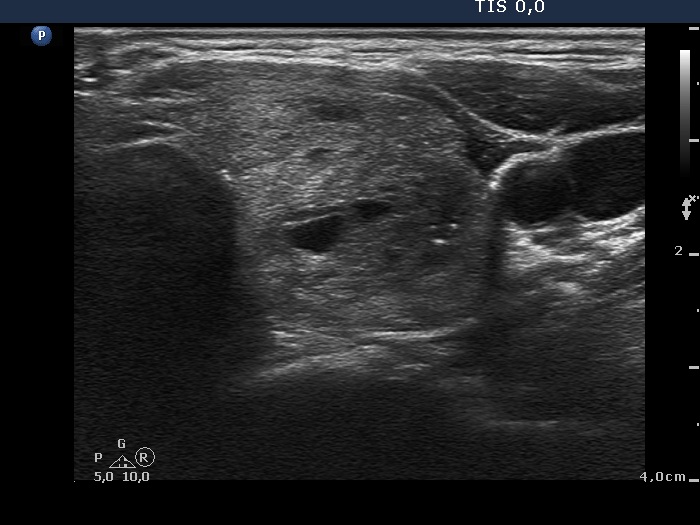

Palpation: Both lobes were enlarged and nodular on palpation.

Ultrasonography. The thyroid was echonormal. There were multiple nodules in both lobes including one containing hypoechogenic areas and hyperechogenic granules corresponding to microcalcifications.

Comment. This case illustrates the importance of the measurement of the entire lobes. The thyroid was composed of multiple nodules and it is impossible to measure reproducibly the single nodules. Moreover, as in most cases not the volume of a single nodule but that of the entire thyroid or that of a lobe will decide the issue of surgery. If we do not give the three diameters of each lobe than we divest the patient of the most important parameter for a follow-up investigation.